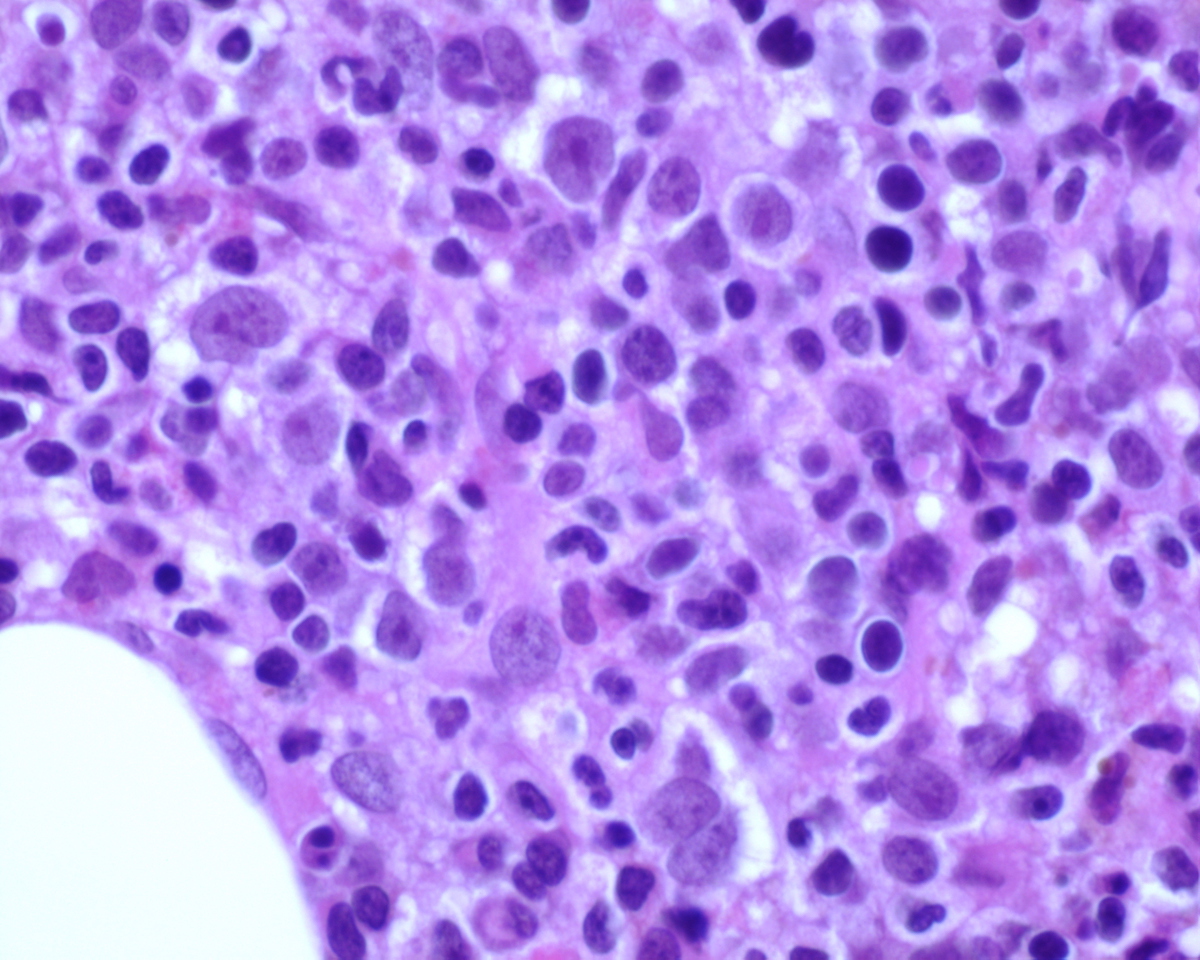

Bone marrow aspirate direct and particle smears, blood clot, right iliac crest biopsy and accompanying peripheral blood smear were received. The peripheral blood, direct and particle smears were stained with Wright-Giemsa stain. The clot and core biopsy were fixed in 10% buffered formalin and the biopsy was decalcified in formic acid bone decalcifier (Immunocal). The peripheral blood smear shows pancytopenia with anisocytosis, and a leukoerythrobastic reaction. No Auer rods are noted on the circulating blasts. Occasional neutrophils appear dysplastic with hypogranulation and hyposegmentation. The bone marrow smears were hemodilute and showed no significant dyspoiesis in the erythroid and granulocytic series. Megakaryocytes were predominantly small sized and left shifted. The decalcified bone marrow biopsy is hypercellular for age with markedly increased immature precursors with prominent nucleoli. The few fully mature megakaryocytes present do not show morphologic features associated with ET. Increased numbers of micromegakaryocytes as well as small, left shifted megakaryocytes are present.

Immunohistochemical stains showed marked increase of megakaryocytes, including numerous small, monolobated forms, which are strongly positive for CD61. CD34 and CD117 highlight increased immature cells, approximately 10% of the nucleated marrow elements. Reticulin shows mild diffuse increase in fiber deposition. An iron stain shows adequate stainable iron. Immunophenotyping by flow cytometry reveals approximately 7% of the total gated events in the dim CD45 positive gate, which coexpress CD34, CD117 and myeloid antigens. A subset of the cells coexpress CD41 and CD61 indicating megakaryocytic lineage.

| Core BX high power 40X | ![]() |

| Core BX high power 60X | ![]() |